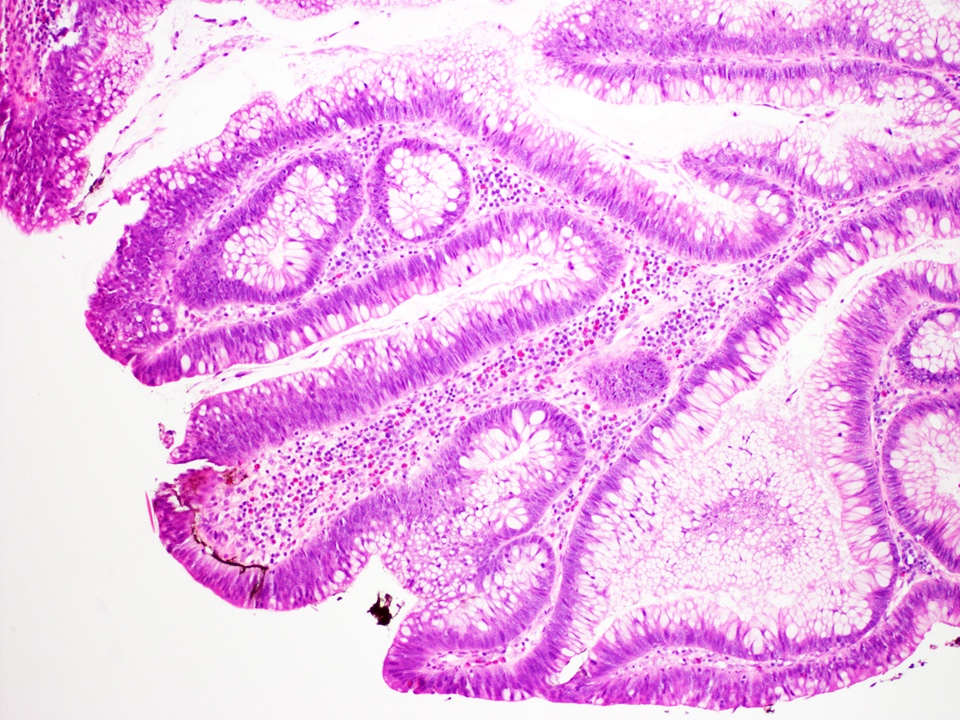

Microscopic (histologic) description

- Low grade dysplasia:

- Preserved nuclear polarity

- Pseudostratified, crowded, elongated and hyperchromatic nuclei

- Lack of surface maturation, i.e. abnormalities persist to surface

- Features distinguishing IBD associated polypoid dysplasia and sporadic adenomas have been described but are not reliable and have no therapeutic implications

- Include lamina propria inflammation, mixture of benign and dysplastic glands at the surface and dysplasia in stalk of polyp (Hum Pathol 1983;14:931, Am J Surg Pathol 1998;22:275)

- Distinction is also not clinically significant as endoscopic polypectomy suffices either way

Microscopic (histologic) images